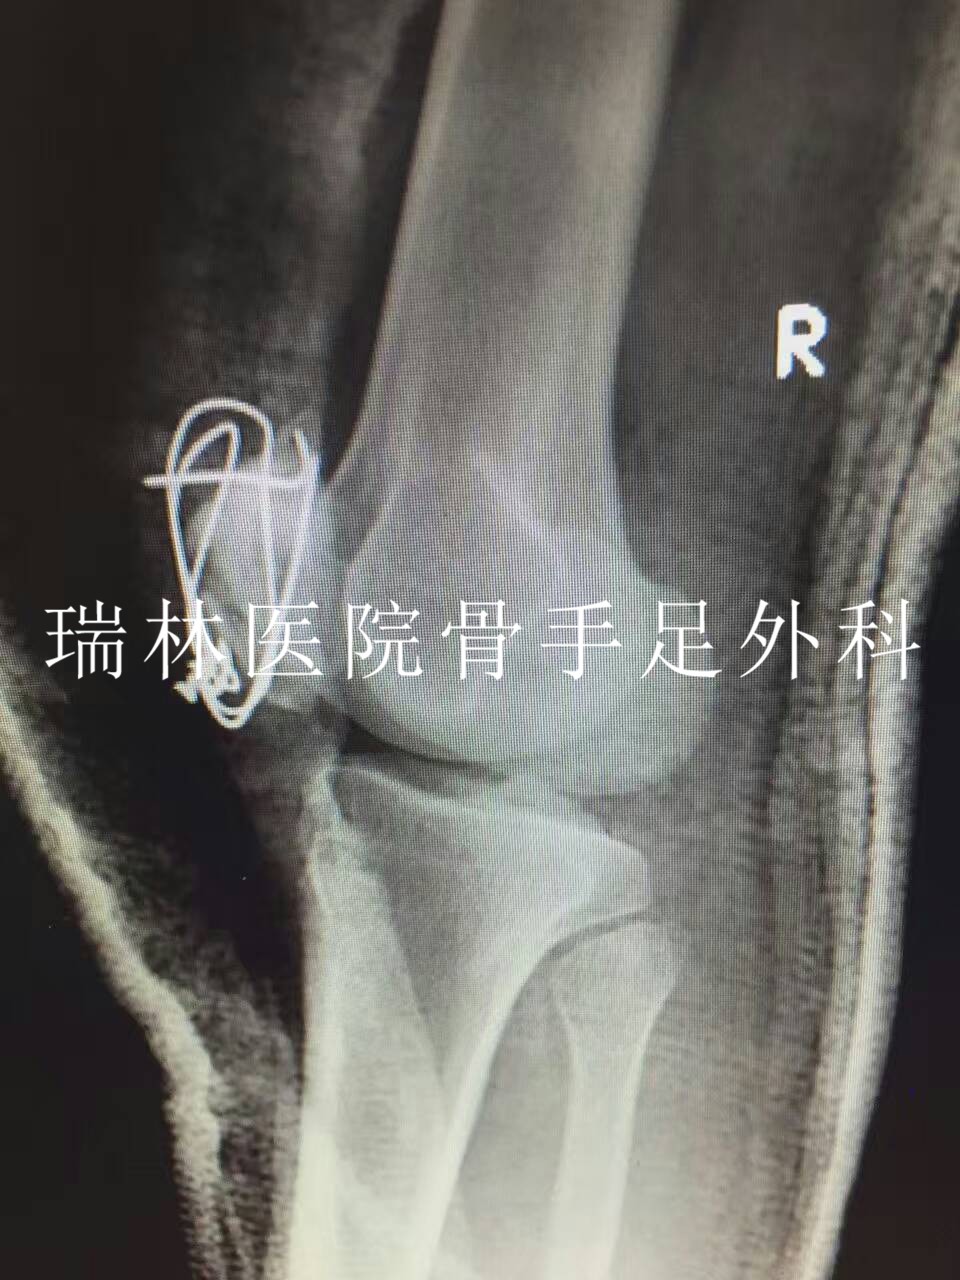

李XX断肢再植手术